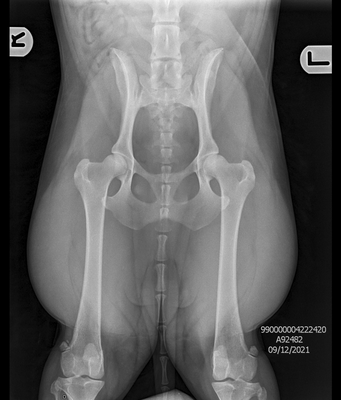

Hip & Elbow x-rays

Perhaps one of the most well known health testing in dogs, hip and elbow x-rays taken to check for signs of dysplasia. Once taken by a qualified vet the x-rays are then sent to a scoring board dependent on country of residence or personal choice of the breeder. To the right, is a comparison of the results across the most common available testing organisations.

The organisation which we primarily use for our program is BVA.

Hips: Under the BVA scheme, the marking of hips is broken down into 9 sections, the maximum marks in any one section is 6, and the maximum overall is 106. The aim is to obtain the combined lowest number possible, the best result possible being a 0. Please view the example images of our dogs results attached above to see the 9 possible sections.